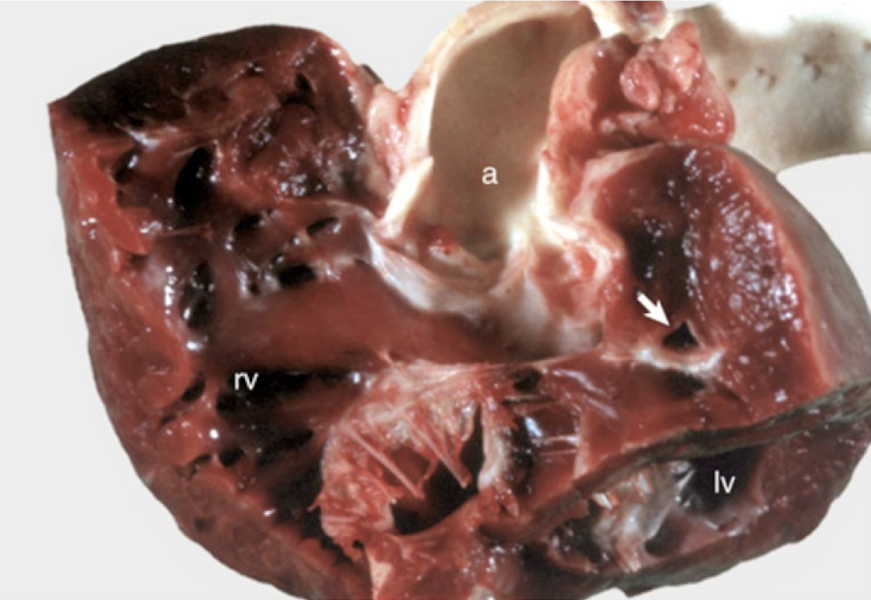

<p>What is this showing?</p>

What is this showing?

atrial septal defect